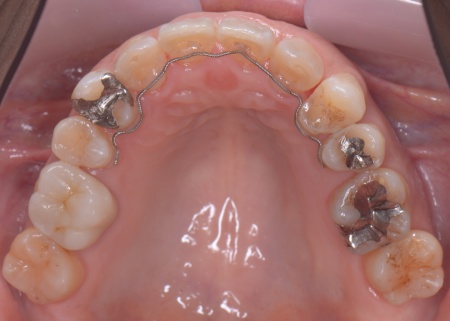

①上あごの骨が狭く歯が並ぶスペースが不足しているため、まず上あごの骨の幅を広げる急速拡大装置を装着する。

成人になってからの骨の拡大は難しいものの、あごの骨に矯正用の小さなネジを埋め、そこを固定源として効率的に歯を動かす治療を併用することでスムーズに拡大を進める。

②①と並行して上下歯列にワイヤー矯正のマルチブラケット装置を装着し、歯並びと噛み合わせを整える。